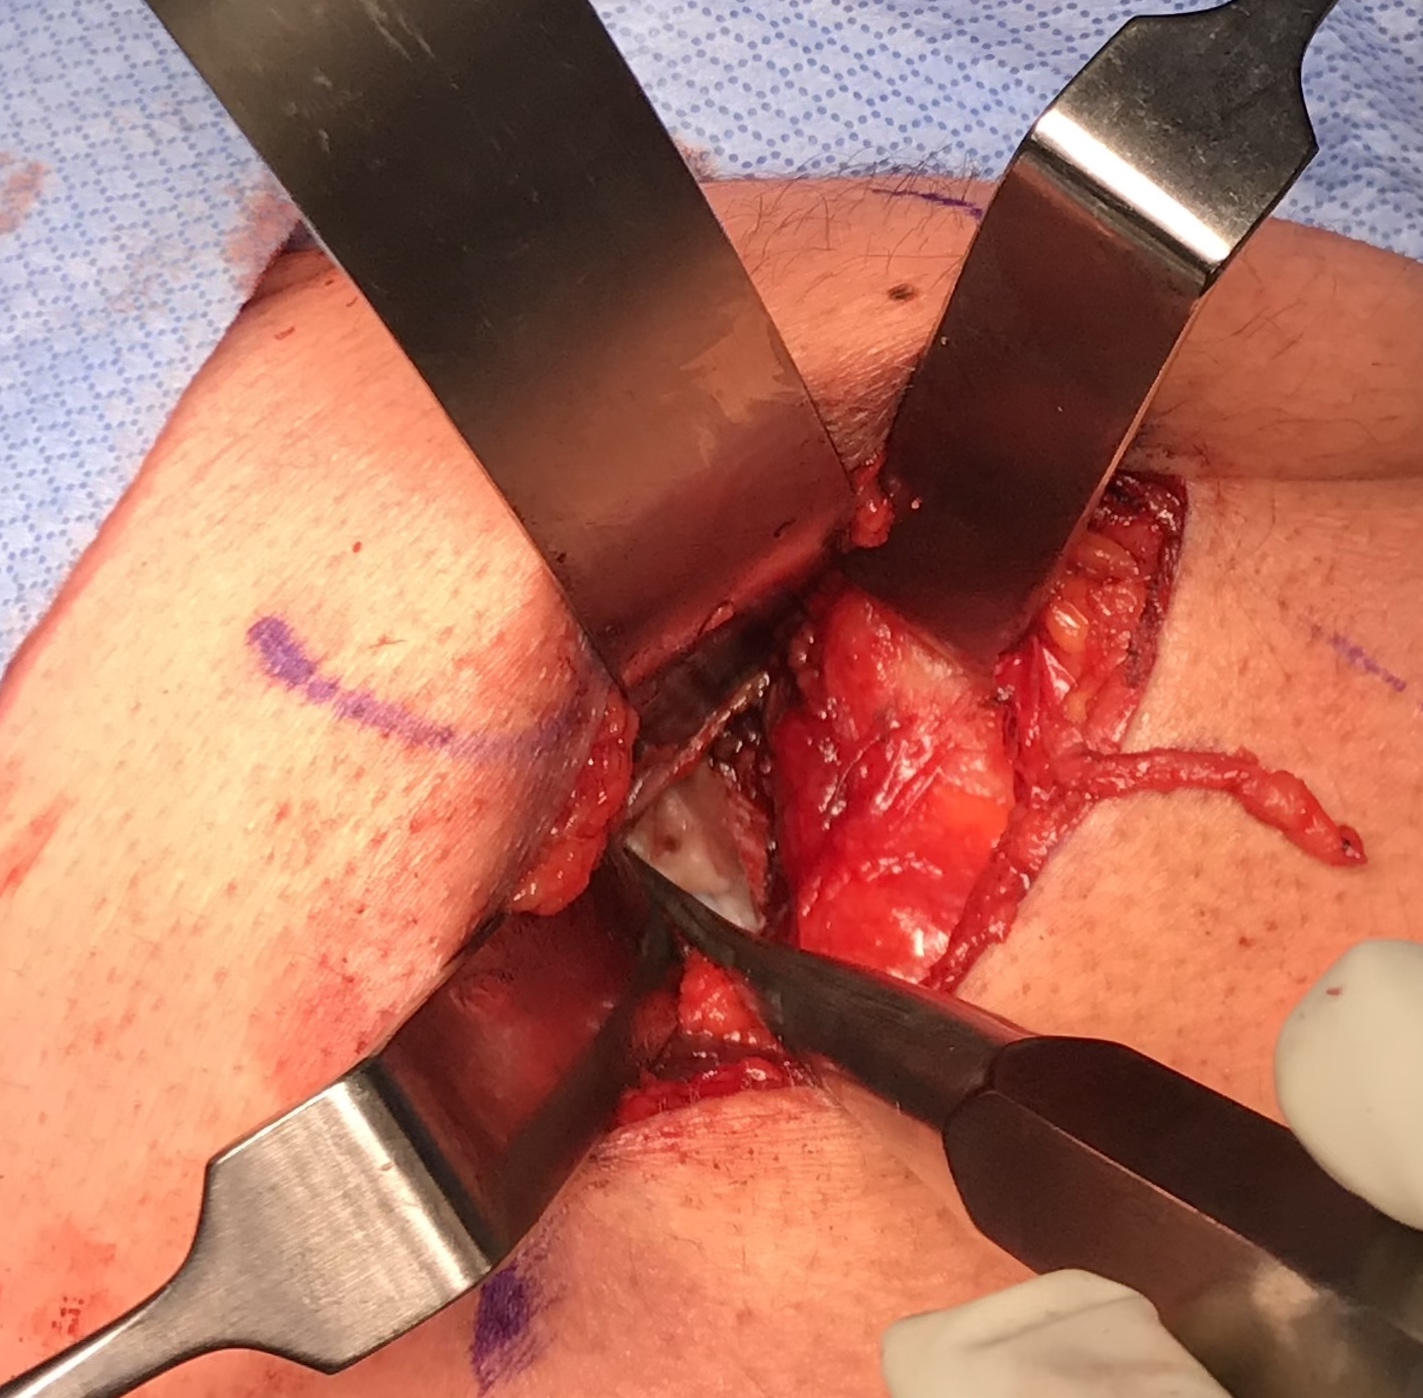

Expose ischial tuberosity

- superior retractor on ischial tuberosity

- medial and lateral retractors, care with sciatic nerve

- use osteotomes to create bleeding

- 2 - 3 suture anchors, double loaded

Exposing ischial tuberosity (*) with Cobb retractor